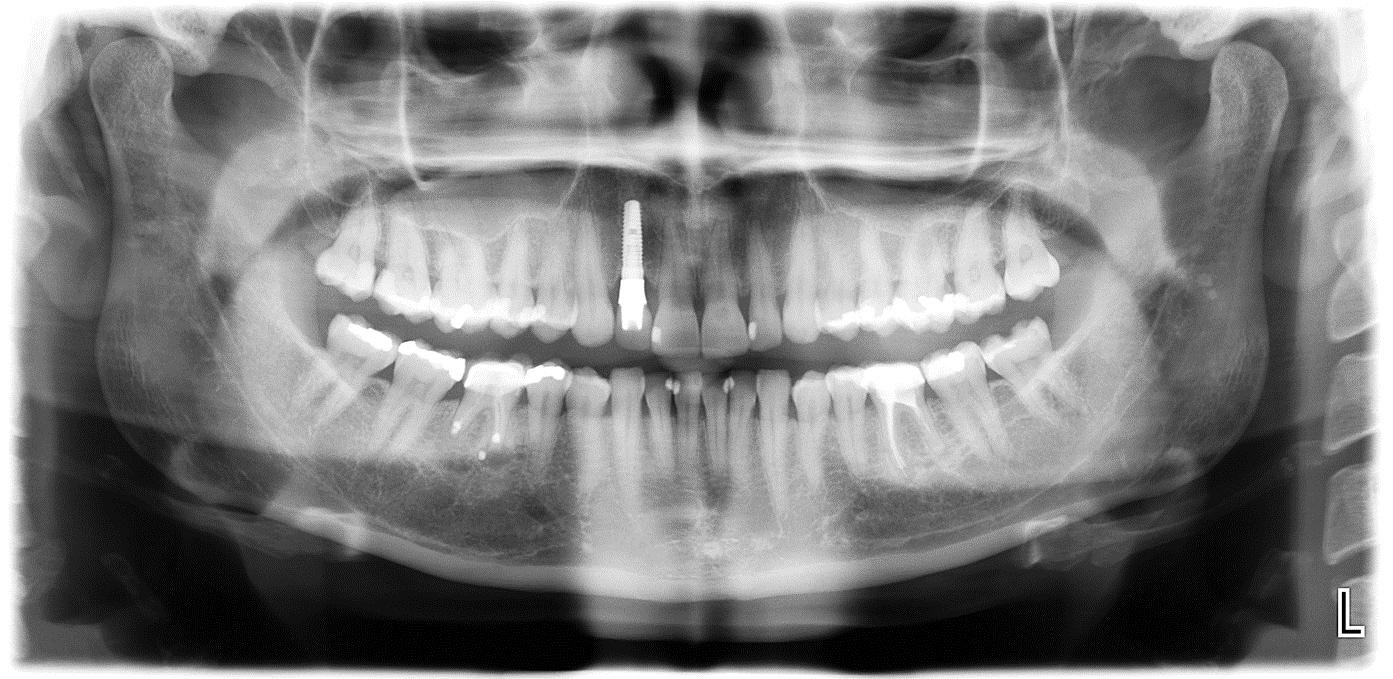

Diagnostik von toten Zähnen in unserer Praxis

In unserer Praxis arbeiten wir mit DVT dreidimensionalen Röntgenbildern, um den Grad der Entzündungen des wurzelkanalbehandelten Zahns genau zu bestimmen.

In bestimmten Fällen, wird zusätzlich eine CaviTau- Aufnahme und ein Labortest „Effektorzelltypisierung auf Mercaptane und Thioether“ gemacht. (Die Effektorzelltypisierung auf Mercaptane und Thioether zeigt durch die Zytokine (TH1-IFN-γ /Treg-IL-10)

an, ob zum aktuellen Zeitpunkt eine Immunreaktion gegen diese Substanzen stattfindet.)